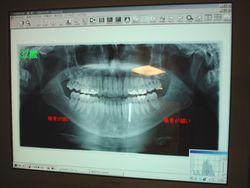

●デジタルX線装置

最新デジタル装置になり、従来のX線装置に比べ、最大1/10に放射線照射量を低減します。 それにより患者様の負担が無くなります。